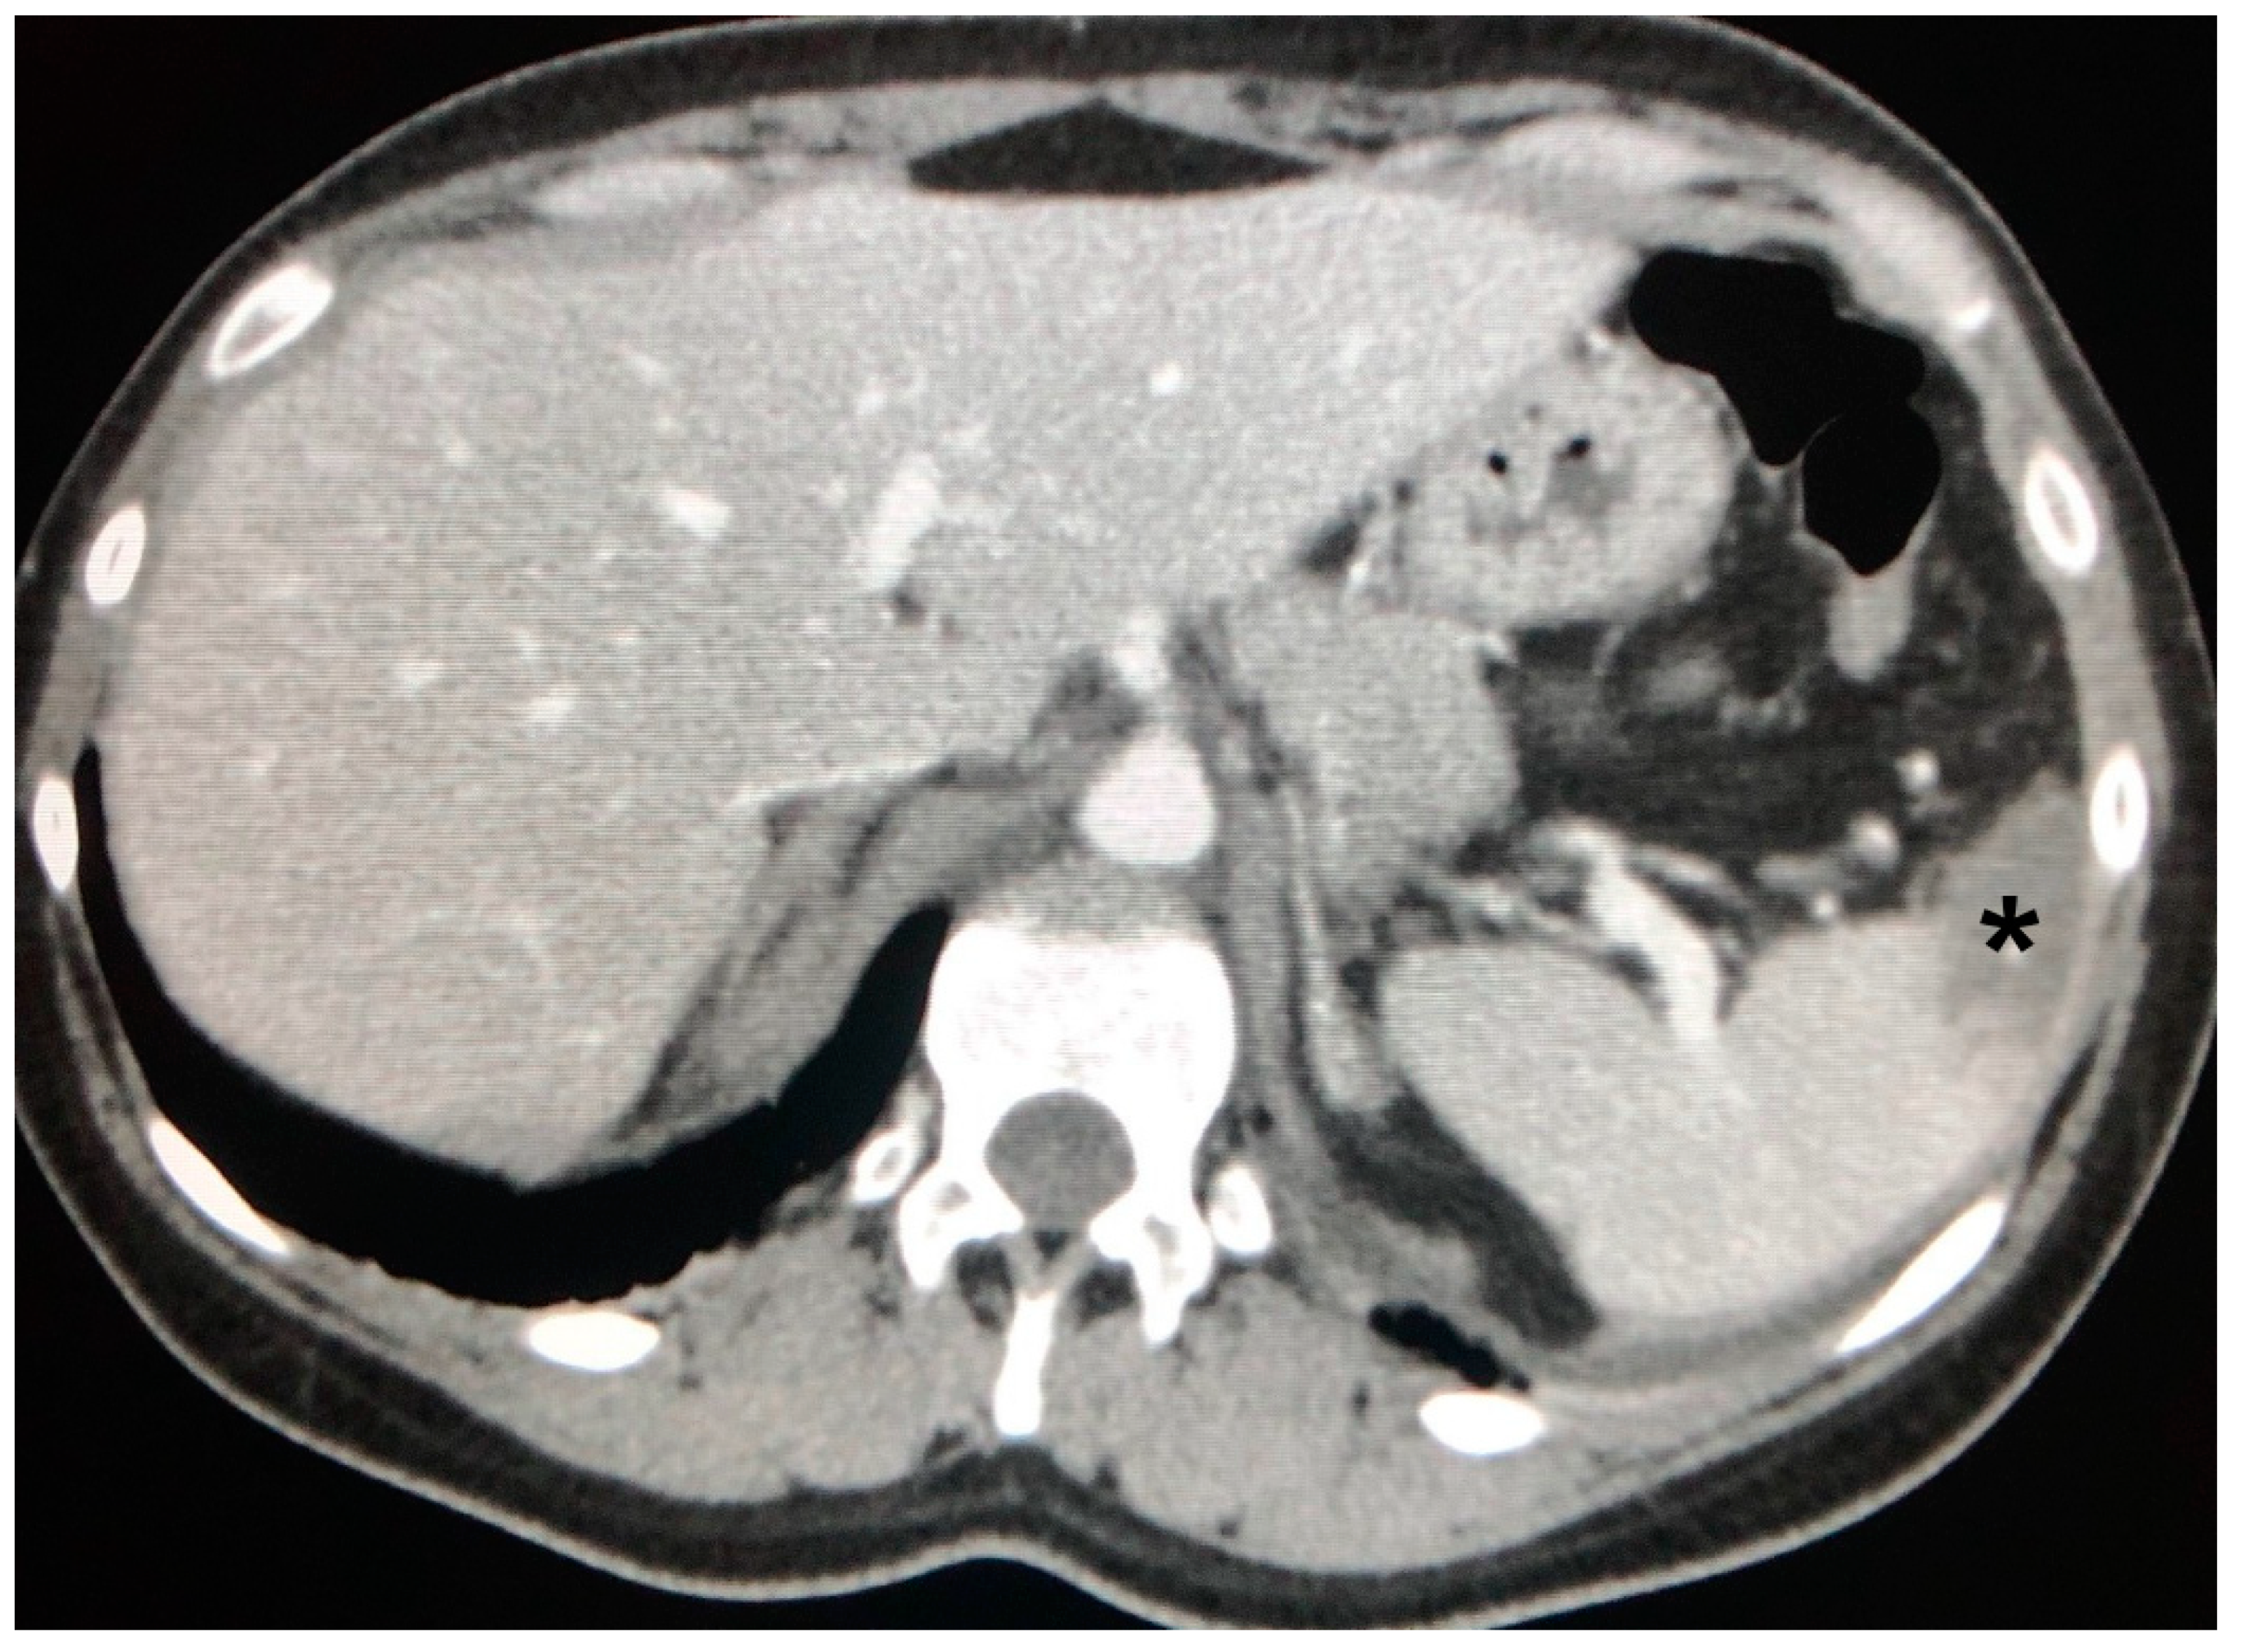

4.1. The Involvement of Liver, Spleen and Abdominal Lymph Nodes

- Palmucci, S.; Torrisi, S.; Caltabiano, D.C.; Puglisi, S.; Lentini, V.; Grassedonio, E.; Vindigni, V.; Reggio, E.; Giuliano, R.; Micali, G.; et al. Clinical and radiological features of extra-pulmonary sarcoidosis: A pictorial essay. Insights Into Imaging 2016, 7, 571–587. [Google Scholar] [CrossRef]

- Warshauer, D.M.; Lee, J.K.T. Imaging Manifestations of Abdominal Sarcoidosis. Am. J. Roentgenol. 2004, 182, 15–28. [Google Scholar] [CrossRef]

- Warshauer, D.M.; Molina, P.L.; Hamman, S.M.; Koehler, R.E.; Paulson, E.K.; Bechtold, R.E.; Perlmutter, M.L.; Hiken, J.N.; Francis, I.R.; Cooper, C.J. Nodular sarcoidosis of the liver and spleen: Analysis of 32 cases. Radiology 1995, 195, 757–762. [Google Scholar] [CrossRef] [PubMed]